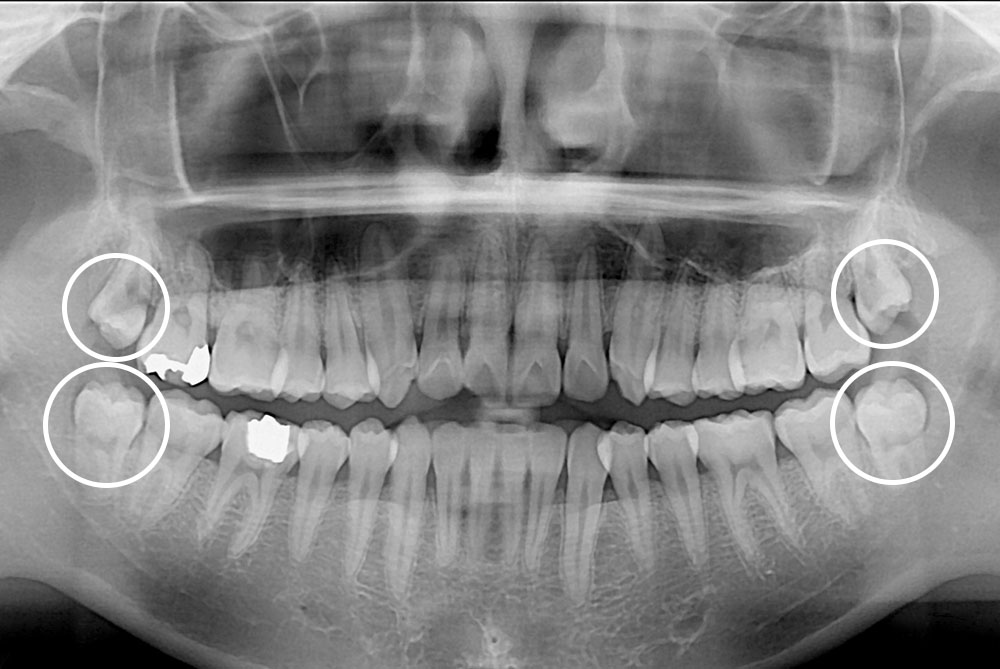

[사랑니] 매복 사랑니 발치

치료전 : 2019-04-04